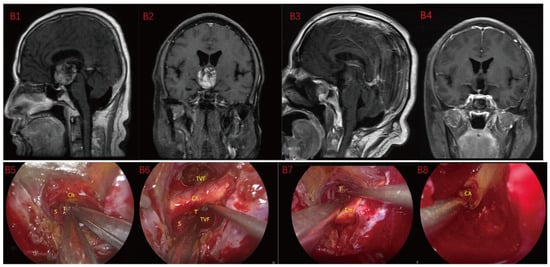

Figure 2.

Case 2: Type II: The tumor located on the suprasellar region and compressed or penetrated the third ventricle floor (TVF) (A1,A2). During EEA surgery, the complete pituitary stalk can be seen via TCPCA, and the tumor is located behind and above the pituitary stalk (A5,A6). The tumor adhered closely to the floor of the third ventricle, and part of it protruded into the third ventricle during the operation. The tumor achieved GTR (A7). Postoperative MRI were shown in (A3,A4). Optic chiasm (Ch), foramen of Monroe, massa intermedia (MI), cerebral aqueduct (CA), tumor (T), pituitary stalk (S).